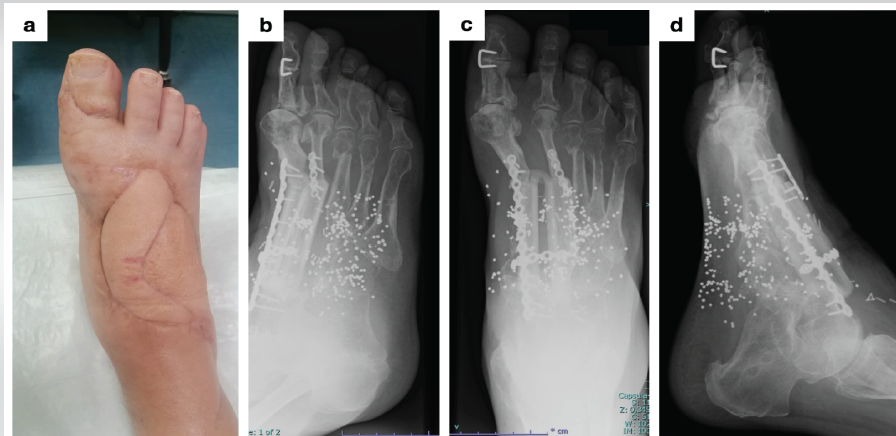

Figure 2: Reconstructive surgery in Case 1. (a and b) Preoperative planning for reconstruction with an osteofasciocutaneous vascularized fibular graft. (c and d) Clinical photograph and X-ray of the foot after surgery.

Subsequent procedures included removal of the external fixator and arthrodesis of the interphalangeal (IP) joint of the hallux, due to failure of the tenodesis. Partial weight bearing was allowed for 1 month, followed by full weight bearing. At 24-month follow-up, radiographs confirmed complete bone consolidation (Fig. 3). The patient was able to walk wearing normal shoes with a customized insole, without the aid of crutches, and without pain or limp.

Figure 3: 24-month follow-up in Case 1. (a) Clinical photograph showing skin condition. (b-d) X-rays of the foot.

During hospitalization, the initial antibiotic regimen included amoxicillin/clavulanic acid, gentamicin, and metronidazole, later modified to sulfamethoxazole combined with trimethoprim, following the identification of Enterobacter cancerogenous colonies. No further clinical signs of infection or bacterial growth were observed. The patient subsequently underwent reconstruction with an osteofasciocutaneous vascularized fibular graft. This included removal of the bone cement and remaining devitalized bone fragments, with harvesting of a contralateral osteofasciocutaneous fibula measuring 16.5 cm. Of this, 6.5 cm were used to reconstruct the first metatarsal and 7.5 cm for the second metatarsal, with a 2.5 cm interposed gap to avoid kinking of the pedicle during flap doubling. Flap insetting was stabilized with internal osteosynthesis using 2.0 mm plates and monocortical screws. Microvascular end-to-end anastomoses were performed between the flap pedicle and the anterior tibial artery and accompanying veins. A tenodesis of the distal tendon of the extensor hallucis longus to the extensor digitorum longus was also performed (Fig. 2).